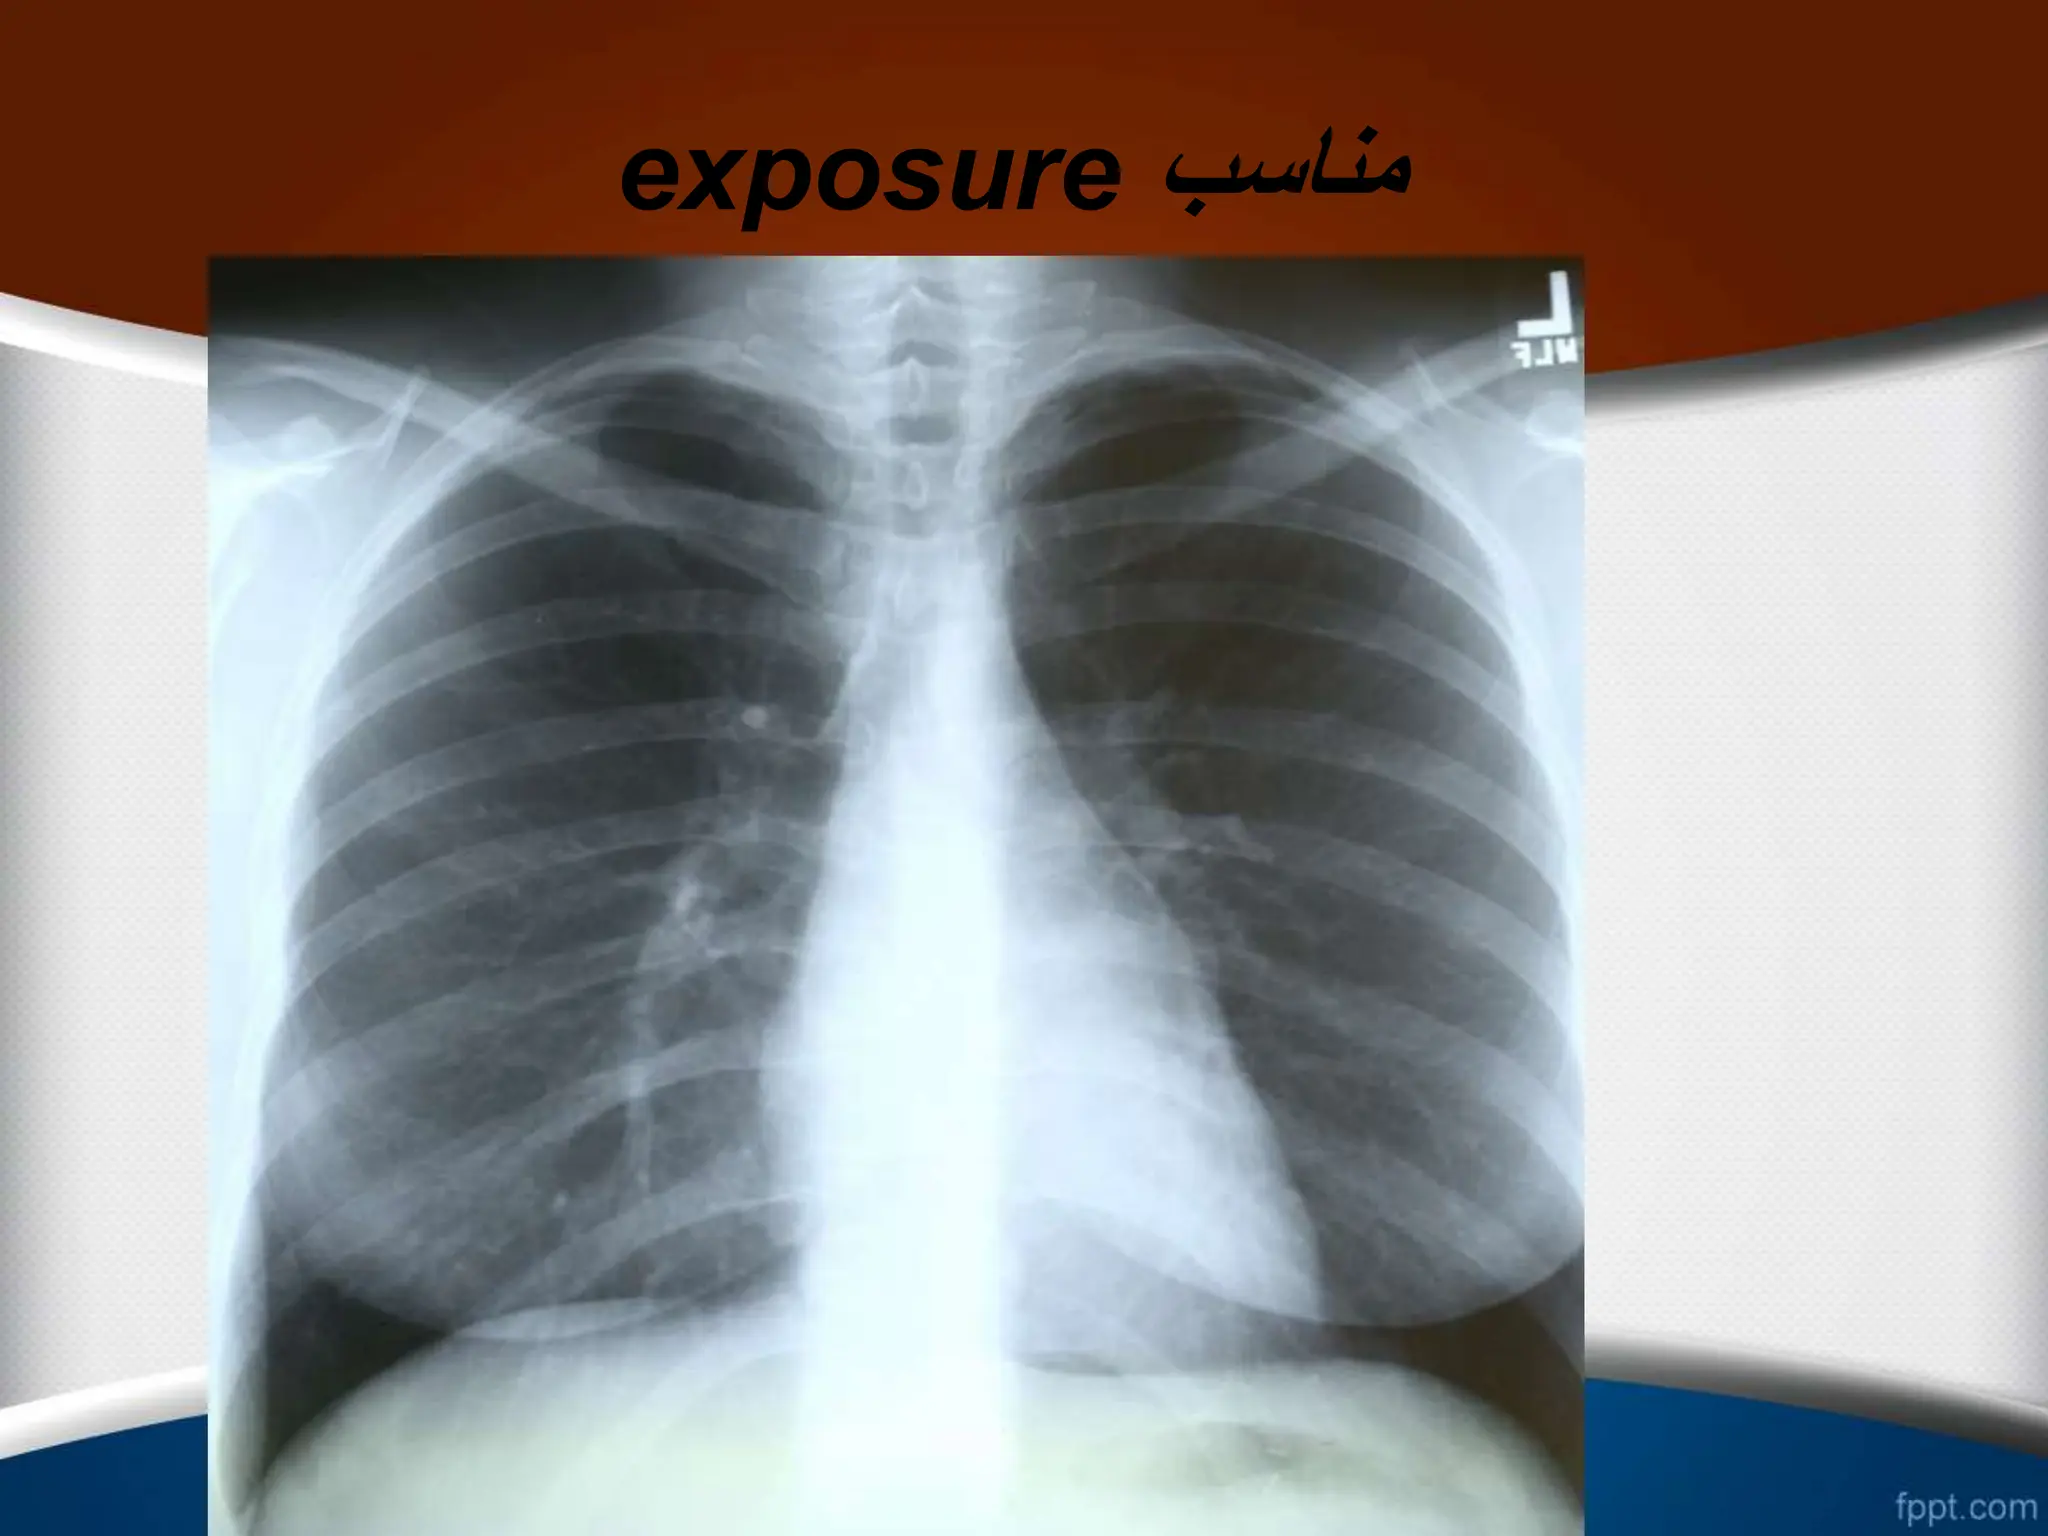

Exposure ‫قرار‬ ‫اشعه‬ ‫معرض‬ ‫در‬ ‫میزان‬ ‫یا‬

‫دنده‬ ‫و‬ ‫ریوی‬ ‫عروق‬ ،‫فقرات‬ ‫ستون‬ ‫مشاهده‬

‫است‬ ‫اشعه‬ ‫میزان‬ ‫بودن‬ ‫مناسب‬

‫به‬ ‫را‬ ‫ها‬ ‫مهره‬ ‫بین‬ ‫فضای‬ ‫نباید‬ ‫مناسب‬ ‫اشعه‬ ‫میزان‬ ‫در‬

.

‫تا‬ ‫ریه‬ ‫عروقی‬ ‫طرح‬

‫شود‬ ‫رؤیت‬ ‫ریه‬ ‫محیط‬ ‫به‬

exposure ‫مناسب‬